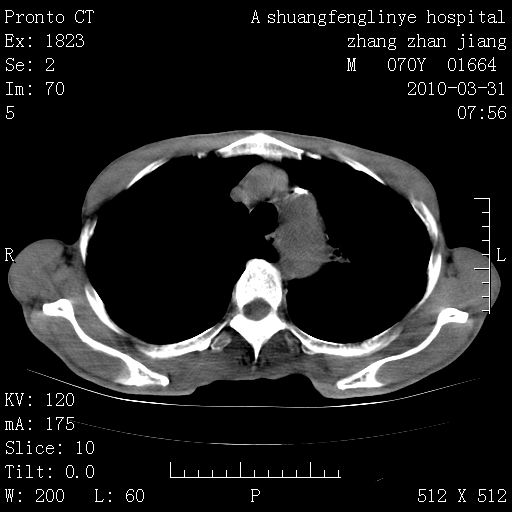

双上肺继发型tb并左上空洞形成,主动脉冠脉钙化。

支持:继发性肺结核伴空洞形成!建议纤支镜检查待出外周围型肺癌可能!

1)两肺上叶继发性肺结核并左肺上叶空洞形成。2)冠状动脉及主动脉钙化。